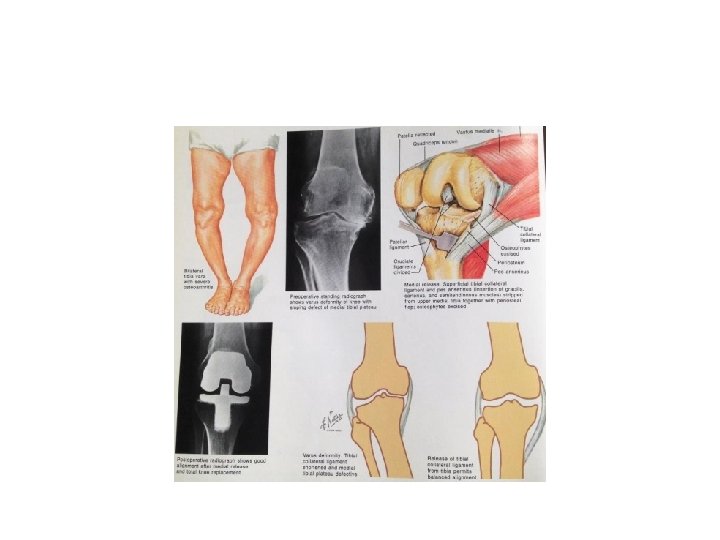

Knee deformity : -Bow legs(Genu varum)and Knock knees(Genu valgum) BY the end of growth, the knees are normally in 5 -7 degrees of valgus, so any thing more or less than that would be classified as deformity. In general, deformity is usually can be noticed by simple observation, this is best done with the Bilateral genu varum(bow leg) can be recorded by measuring the distance between the knees with the legs straight and the medial malleoli just touching; it should be less than 6 cm. Genu valgum(knock knee) can be recorded by measuring the distance between the medial malleoli when the knees are held touching with patellae facing forwards; it is usually less than 8 cm. patient standing and bearing weight.

Genu varum and valgum

Bone dysplasias and rickets are associated with more intractable deformities which needed operative correction. Blount's disease is aprogressive bow leg deformity associated with abnormal growth of the posteromedial part of the proximal tibia, children are often overweight and start walking early; deformity is usually bilateral and rotational element. ethe epiphysis. spontaneous resolution is rare and operative correction is usually needed. Valgus and varus deformities in adults –especially if they are unilateral are likely due to rheumatoied arthritis(valgus) or osteoarthritis(varus). Treatment : slight deformity can be well tolerated but if the deformity is marked or associated with instability, it can be corrected by joint reconstruction or supracondylar femoral osteotomy for valgus and high tibial osteotomy for varus. •